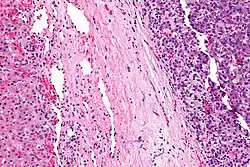

| Micrograph of a hepatoblastoma. H&E stain. | |